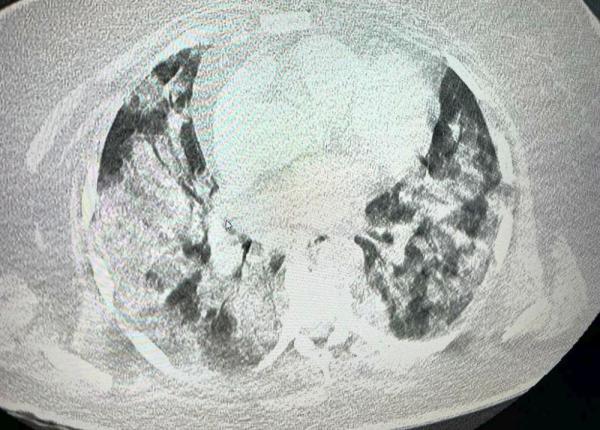

Durerea în piept poate fi un semn al unor afecțiuni grave, precum un atac de cord, embolie pulmonară sau alte probleme cardiace și pulmonare. Primirea asistenței medicale prompte este crucială pentru stabilirea cauzei și pentru inițierea tratamentului adecvat.

Dr. Cristian Pandrea, medic primar medicină de urgență, a explicat ce trebuie să știm despre durerea în piept. Este asociată cu boli grave, precum infarcul, tromboembolismul pulmonar, dar și cu alte afecțiuni care nu pun viața în pericol. De aceea este necesar să ne prezentăm la medic.

"Durerea extrem de intensă are o semnificație importantă și, de fapt, în medicina de urgență ne gândim că atunci când avem o durere în piept la ce e mai rău, adică la bolile care pun în pericol viața pacienților, cum ar fi boala cardiacă ischemică cu situația ei majoră infarctul miocardic, tromboembolismul pulmonar care reprezintă o afecțiune vasculară, adică un cheag în circulația pulmonară.

Poate fi o patologie vasculară, adică o disecție de aortă, o ruptură la nivelul peretelui aortei, care este artera centrală la nivelul organismului. Aceste trei entități sunt imediat amenințătoare de viață și trebuie să facem gesturi care să se întâmple repede și să fie eficiente.